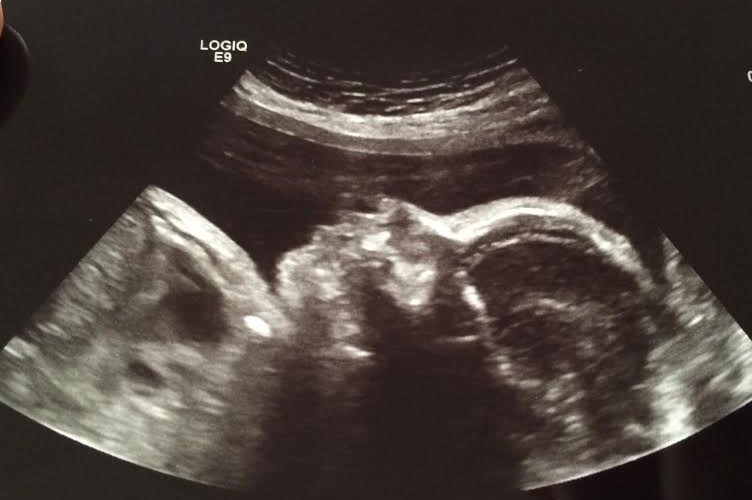

we had an appointment yesterday and the ultrasound technician estimated her to weigh about 3 pounds, 3 ounces! in the 56th percentile!

best moment this week: we had a wonderful time with both of our families for Thanksgiving! I made this salted caramel apple pie for both houses! so yummy! we got lots of baby shower crafts done on friday, organized little miss’ closet and went wedding dress shopping with my SIL! so much progress and fun over the long weekend! {and since I’m late posting…we also got to see her in an ultrasound yesterday! she has gotten so big…it amazes me everytime!}